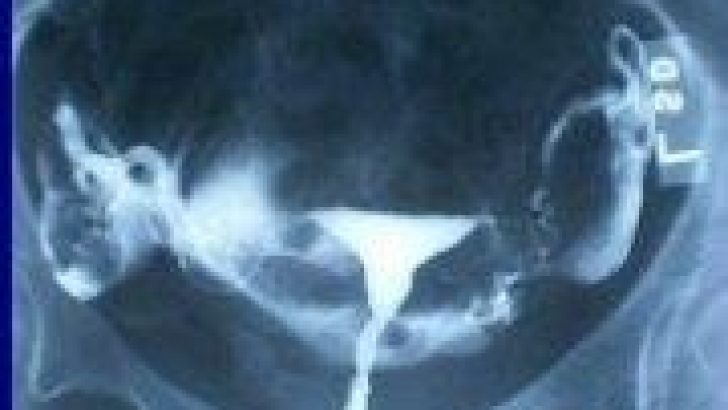

Медицинские снимки: Проходимость маточных труб